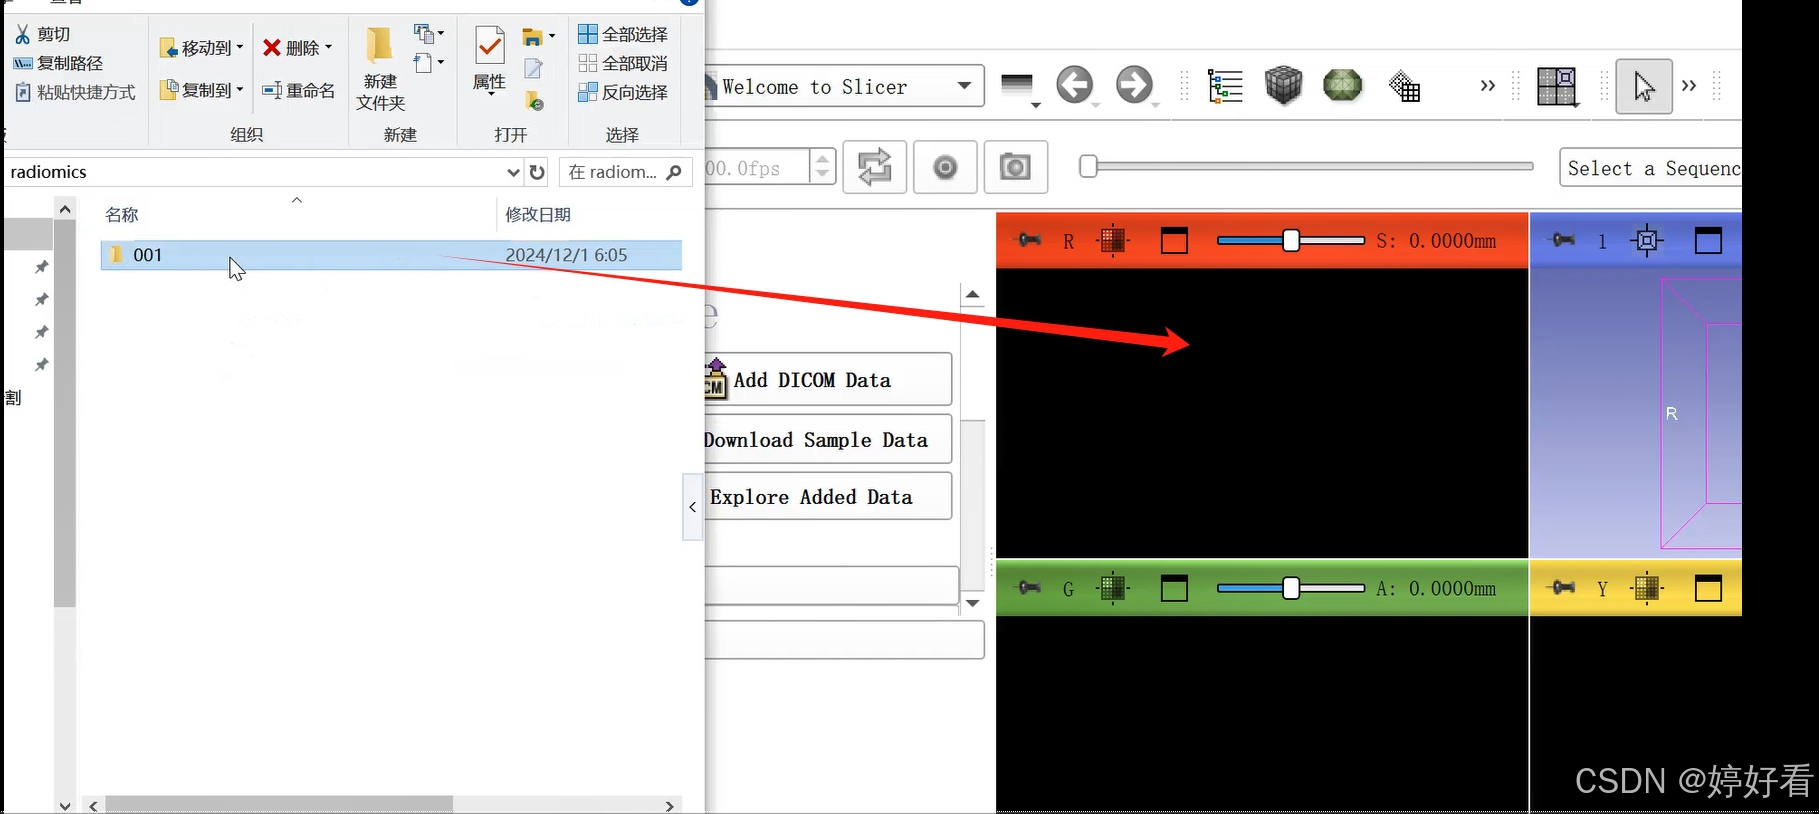

1、添加数据

1.1 首先,把包含DICOM格式影像图片的文件夹直接拖到3D slicer的界面,然后点击OK。